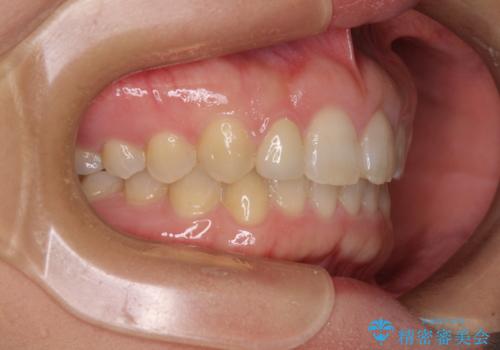

前歯の歯並びと小さい歯を改善 インビザラインとオールセラミッククラウン

- 前歯の空隙と矮小歯を気にして来院された患者様です。

上下の歯列不正はインビザラインにより整えることとしました。

矯正治療の後に、前歯1歯と奥歯をオールセラミックにて治療することとしました。

矯正治療により矮小歯前後にスペースを作りながら歯列を整え、セラミッククラウン装着後に最終的に歯列と咬合を仕上げました。